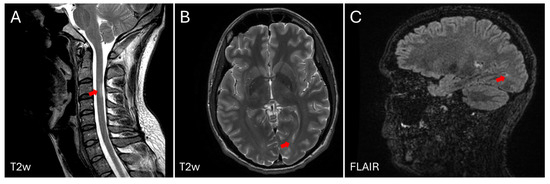

2. Case Description